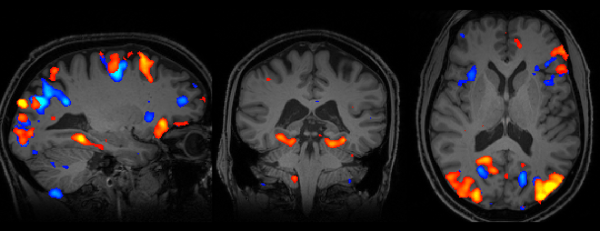

Memory_fMRI

Functional MRI image of the human brain using the MRI Scanner

A person is put in the MRI scanner with headphones on.  They are shown a photo of a person familiar to them, either a friend, family member or celebrity.  Then, in their headphones they are played the voice of a person, but the voice is either sped up or slowed down.

They are required to say whether the face on the photo matches the voice they have heard. What happens in the brain when this confusion of audio and visual information is occurring? Will the brain find a way to identify the vocal signature of the voice, even if distorted, and be able to say with conviction if the photo and the voice are a match?

On the day of the experiment, the winners and runners-up headed over to the WIN Centre to watch Richard’s winning experiment being conducted. The experiment was streamed live by Oxford Sparks and we had a clear result from the test, as neuroscientist Dr Holly Bridge explains:

The scans show that when you’re getting information that corresponds in both your auditory and your visual system you get a boost in your brain activity. We can detect that the brain does respond differently depending on whether or not you can match the face with the voice; it clearly has a lot to do with expectation.